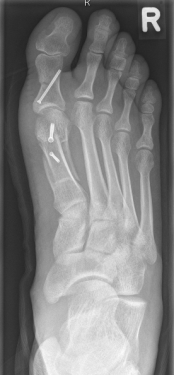

So, nun liege ich also hier, im St. Petrus-Krankenhaus zu Bonn, vor mir zwei Krücken (ja ich weiß, die Dinger heißen Unterarmgehstütze, aber es sagt ja auch kein Mensch ,Lichtzeichenverkehrsanlage‘), Jesus an der Wand – und der operierte Fuß, noch dick verbunden und mit einem gelblichen Zeug bepinselt, nur der Große Zeh und sein Nachbar schauen oben heraus. Dank einer besonderen Betäubung des rechten Beins verlief die Nacht ohne Probleme. Erst heute früh um kurz nach vier meldete er sich zurück, nicht direkt mit Schmerzen, eher mit einem Kribbeln, als ob er sagen wollte: „Hallo, da bin ich wieder!“ Morgen wird zum ersten Mal der Verband gewechselt, bin sehr gespannt, wie es geworden ist. Das erste Röntgenbild gestern sah schon sehr vielversprechend aus.

Von der OP bekam ich dennoch nicht viel mit, weil sie zum Glück hinter einem Sichtschutz ablief, ab und zu mal eine gut gelaunte Stimme und das Sirren der kleinen Motorsäge. Die Kiefer-OP vor sechs Jahren war viel viel schlimmer, vor allem schmerzhafter, DAS war Horror. Nach gut einer Stunde wurde mir – wie einer Entbundenen das Baby – das besagte Röntgenbild überreicht. Dann wurde ich erst in den Aufwachraum gebracht, wo nach wenigen Minuten das linke Bein erwachte, danach zurück ins Zimmer.

Tatsache ist, ich kann nicht viel machen außer hier zu liegen und zu lesen – was nun wirklich nicht das schlechteste ist -, oder fernzusehen, was ich auf das absolut notwendigste beschränke. Ein Gang aufs Klo ist schon eine richtige Anstrengung. Heute Nachmittag bekam ich einen Vorderfuß-Entlastungsschuh, den ich unter therapeutischer Anleitung ausprobierte, sogar mit Treppe. Ziemlich gewöhnungsbedürftig und nicht ganz schmerzfrei das ganze, aber so muss es (bzw. ich) erstmal gehen in den nächsten Wochen. Zum Vergleich: nach der Kiefer-OP konnte ich vier Monate lang nicht zubeißen aus Vorsicht, das Provisorium nicht zu zerlegen, das war viel schlimmer.

Nachher:

Rechts nachher